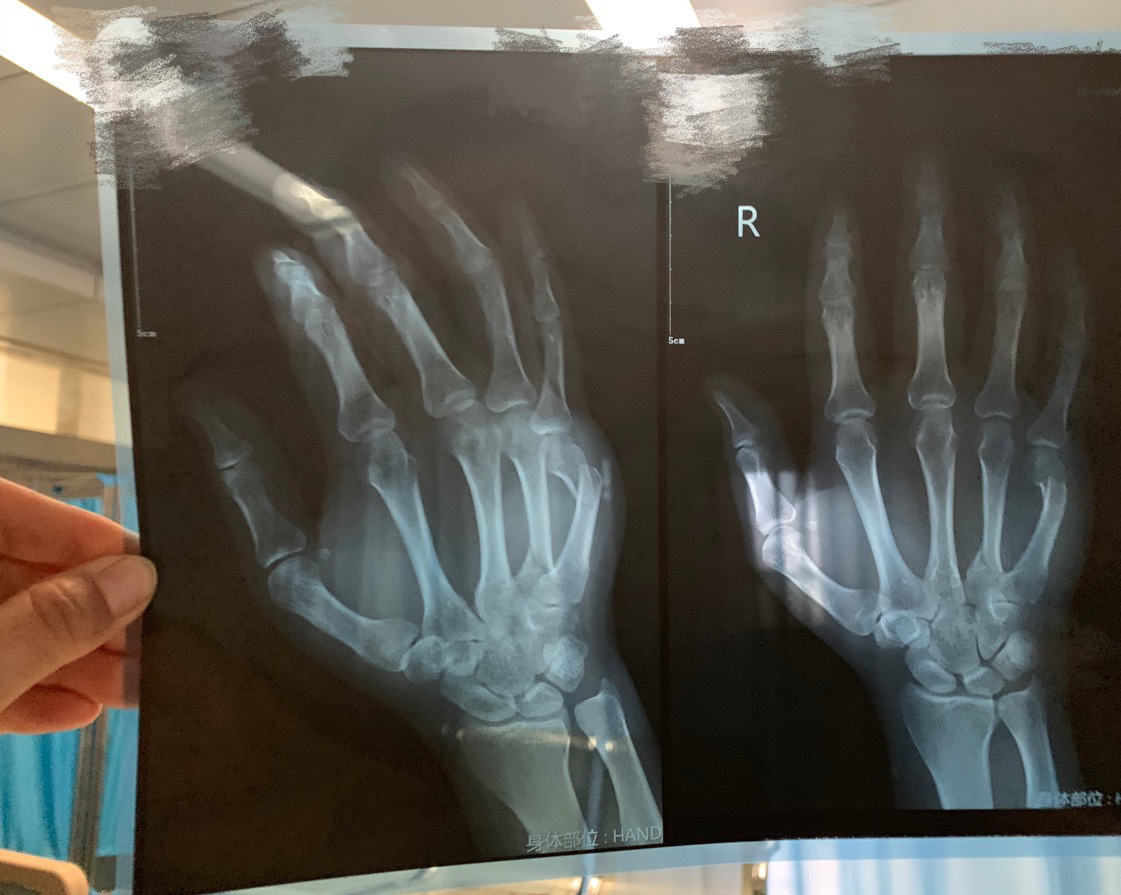

金属过敏的病人骨折错位是否能冒这个险内置钢板!?!

各位大佬来帮忙看看!!!这样的情况是不是必须手术了!!病人不去非要包药,就是怕体内排异手废了